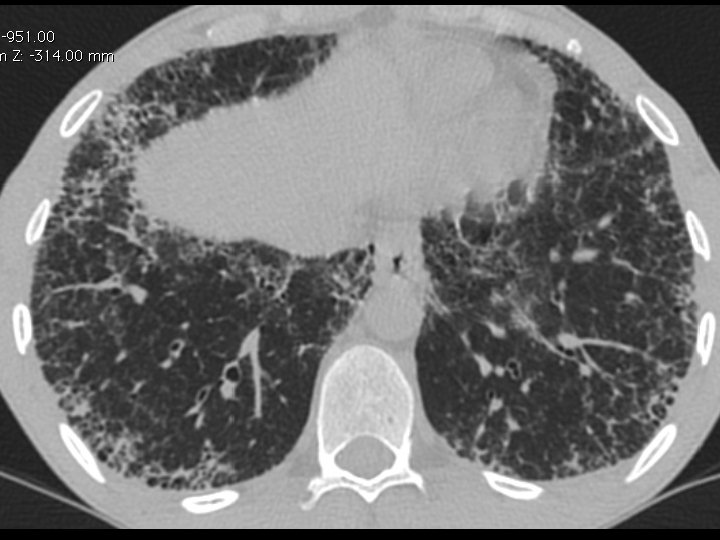

High-resolution CT scan

Subpleural, basal predominance Reticular abnormality Honeycombing with traction bronchiectasis UIPUIP Pattern

Subpleural, basal predominance Reticular abnormality Honeycombing with traction bronchiectasis Profuse micronodules UIPUIP Pattern Inconsistent with UIP Pattern

39 yo caucasian male, works in car collision repair and painting Multiple allergies, Gastroesophageal reflux disease and Thrombocytopenia of unknown etiology Smoker. No drugs CT: Reticular abnormality and honeycombing of subpleural basal predominance + micronodules Lung function tests: decreased diffusion capacity of the lung Blood tests: small increase of ESR and CRP; Autoimmune screening blood tests were normal BAL: normal celularity, with a mild increase in the neutrophil and eosinophil count

39 yo caucasian male, works in car collision repair and painting Multiple allergies, Gastroesophageal reflux disease and Thrombocytopenia of unknown etiology Smoker. No drugs CT: Reticular abnormality and honeycombing of subpleural basal predominance + micronodules Lung function tests: decreased diffusion capacity of the lung Blood tests: small increase of ESR and CRP; Autoimmune Screening Blood Tests were normal BAL: normal celularity, with a mild increase in the neutrophil and eosinophil count Definitive diagnosis can be established? Additional diagnostic tests required? Which tests?